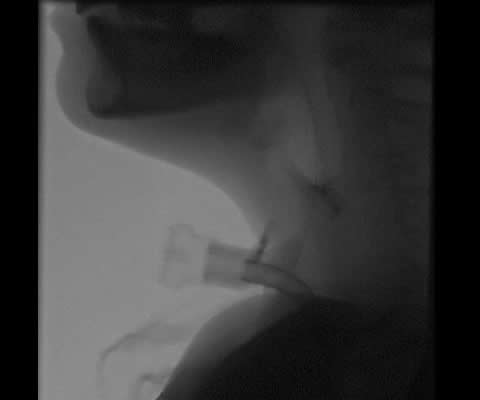

In paediatrics, instrumental assessment is usually performed using Videofluroscopy (VFS). Fig 1 shows different VFS views of a paediatric tracheostomy. Select the numbers to view each image or use the Previous and Next buttons.